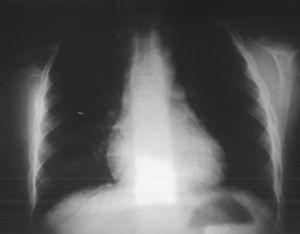

Pruebas complementarias. Radiografía cervical y de tórax (figs. 1 y 2): escápula derecha elevada, apreciándose en columna cervical apéndices costales C6 de predominio derecho.

Figura 2. Radiografía de tórax: escápula derecha elevada.

En la radiografía de tórax, se aprecia una elevación de la escápula de unos 2 cm. Esta deformidad es visible a la inspección física, que correspondería a un grado III 1, sin repercusión aparente sobre la movilidad del hombro, pero que conlleva una lateralización casi constante del cuello y escoliosis sintomática compensatoria, en la columna cervical se observan apéndices costales bilaterales, de predominio derecho, asintomáticos, asociando un pie equinovaro, que está siendo tratado ortopédicamente con buen resultado funcional actualmente.